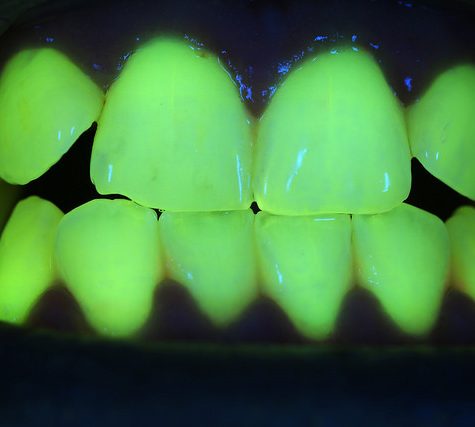

A tooth (plural teeth) is a hard, calcified structure found in the jaws (or mouths) of many vertebrates and used to break down food. Some animals, particularly carnivores, also use teeth for hunting or for defensive purposes. The roots of teeth are covered by gums. Teeth are not made of bone, but rather of multiple tissues of varying density and hardness. The cellular tissues that ultimately become teeth originate from the embryonic germ layer, the ectoderm.

A tooth (plural teeth) is a hard, calcified structure found in the jaws (or mouths) of many vertebrates and used to break down food. Some animals, particularly carnivores, also use teeth for hunting or for defensive purposes. The roots of teeth are covered by gums. Teeth are not made of bone, but rather of multiple tissues of varying density and hardness. The cellular tissues that ultimately become teeth originate from the embryonic germ layer, the ectoderm.

A tooth (plural teeth) is a hard, calcified structure found in the jaws (or mouths) of many vertebrates and used to break down food. Some animals, particularly carnivores, also use teeth for hunting or for defensive purposes. The roots of teeth are covered by gums. Teeth are not made of bone, but rather of multiple tissues of varying density and hardness. The cellular tissues that ultimately become teeth originate from the embryonic germ layer, the ectoderm.

A tooth (plural teeth) is a hard, calcified structure found in the jaws (or mouths) of many vertebrates and used to break down food. Some animals, particularly carnivores, also use teeth for hunting or for defensive purposes. The roots of teeth are covered by gums. Teeth are not made of bone, but rather of multiple tissues of varying density and hardness. The cellular tissues that ultimately become teeth originate from the embryonic germ layer, the ectoderm.

A tooth (plural teeth) is a hard, calcified structure found in the jaws (or mouths) of many vertebrates and used to break down food. Some animals, particularly carnivores, also use teeth for hunting or for defensive purposes. The roots of teeth are covered by gums. Teeth are not made of bone, but rather of multiple tissues of varying density and hardness. The cellular tissues that ultimately become teeth originate from the embryonic germ layer, the ectoderm.

A tooth (plural teeth) is a hard, calcified structure found in the jaws (or mouths) of many vertebrates and used to break down food. Some animals, particularly carnivores, also use teeth for hunting or for defensive purposes. The roots of teeth are covered by gums. Teeth are not made of bone, but rather of multiple tissues of varying density and hardness. The cellular tissues that ultimately become teeth originate from the embryonic germ layer, the ectoderm.